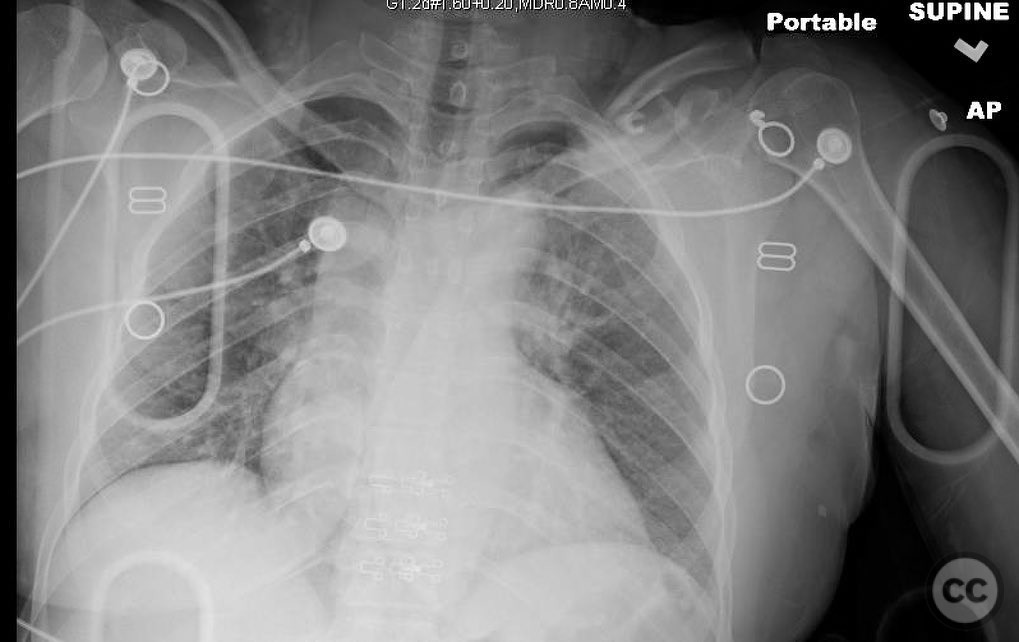

Clinical and radiological findings:  A 35-year-old male presented with an open diaphyseal clavicle fracture following a high-energy motorcycle accident. The fracture was classified as a simple diaphyseal pattern with two butterfly fragments, according to the AO/OTA classification system, specifically 15-B2. The patient exhibited significant soft tissue injury but no neurovascular compromise. Initial radiographs confirmed the fracture pattern, and the wound was thoroughly irrigated and debrided in the emergency department.

Patient positioning:  The patient was positioned supine on the operating table with a small sandbag placed between the scapulae to elevate the shoulder girdle, facilitating access to the clavicle.